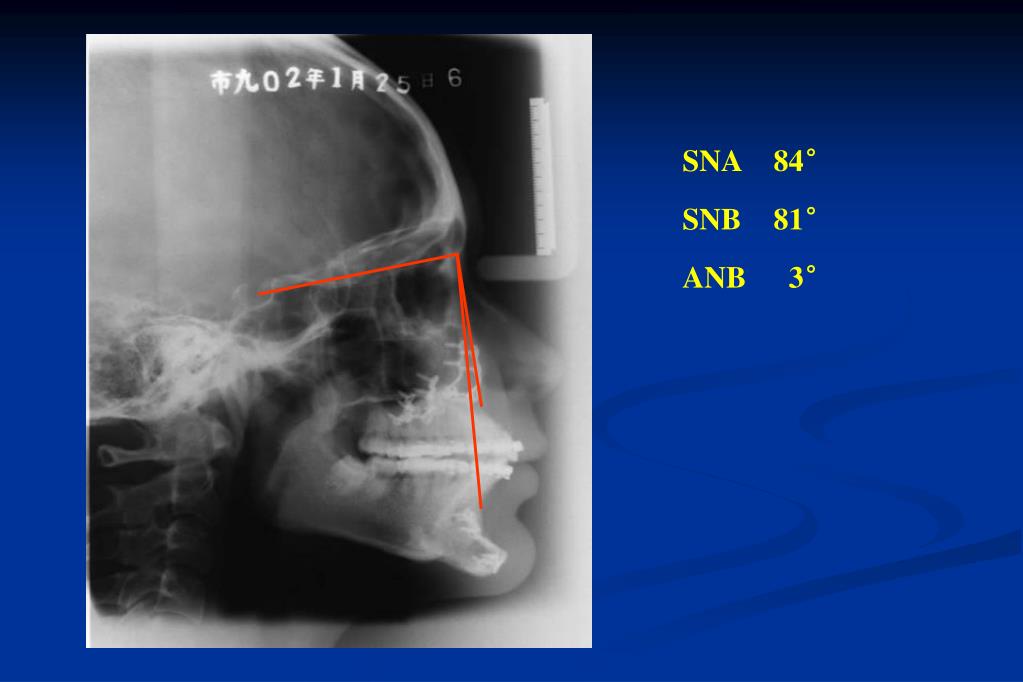

24. Pre treatment

25. SNA 88° SNB 92° ANB 4°